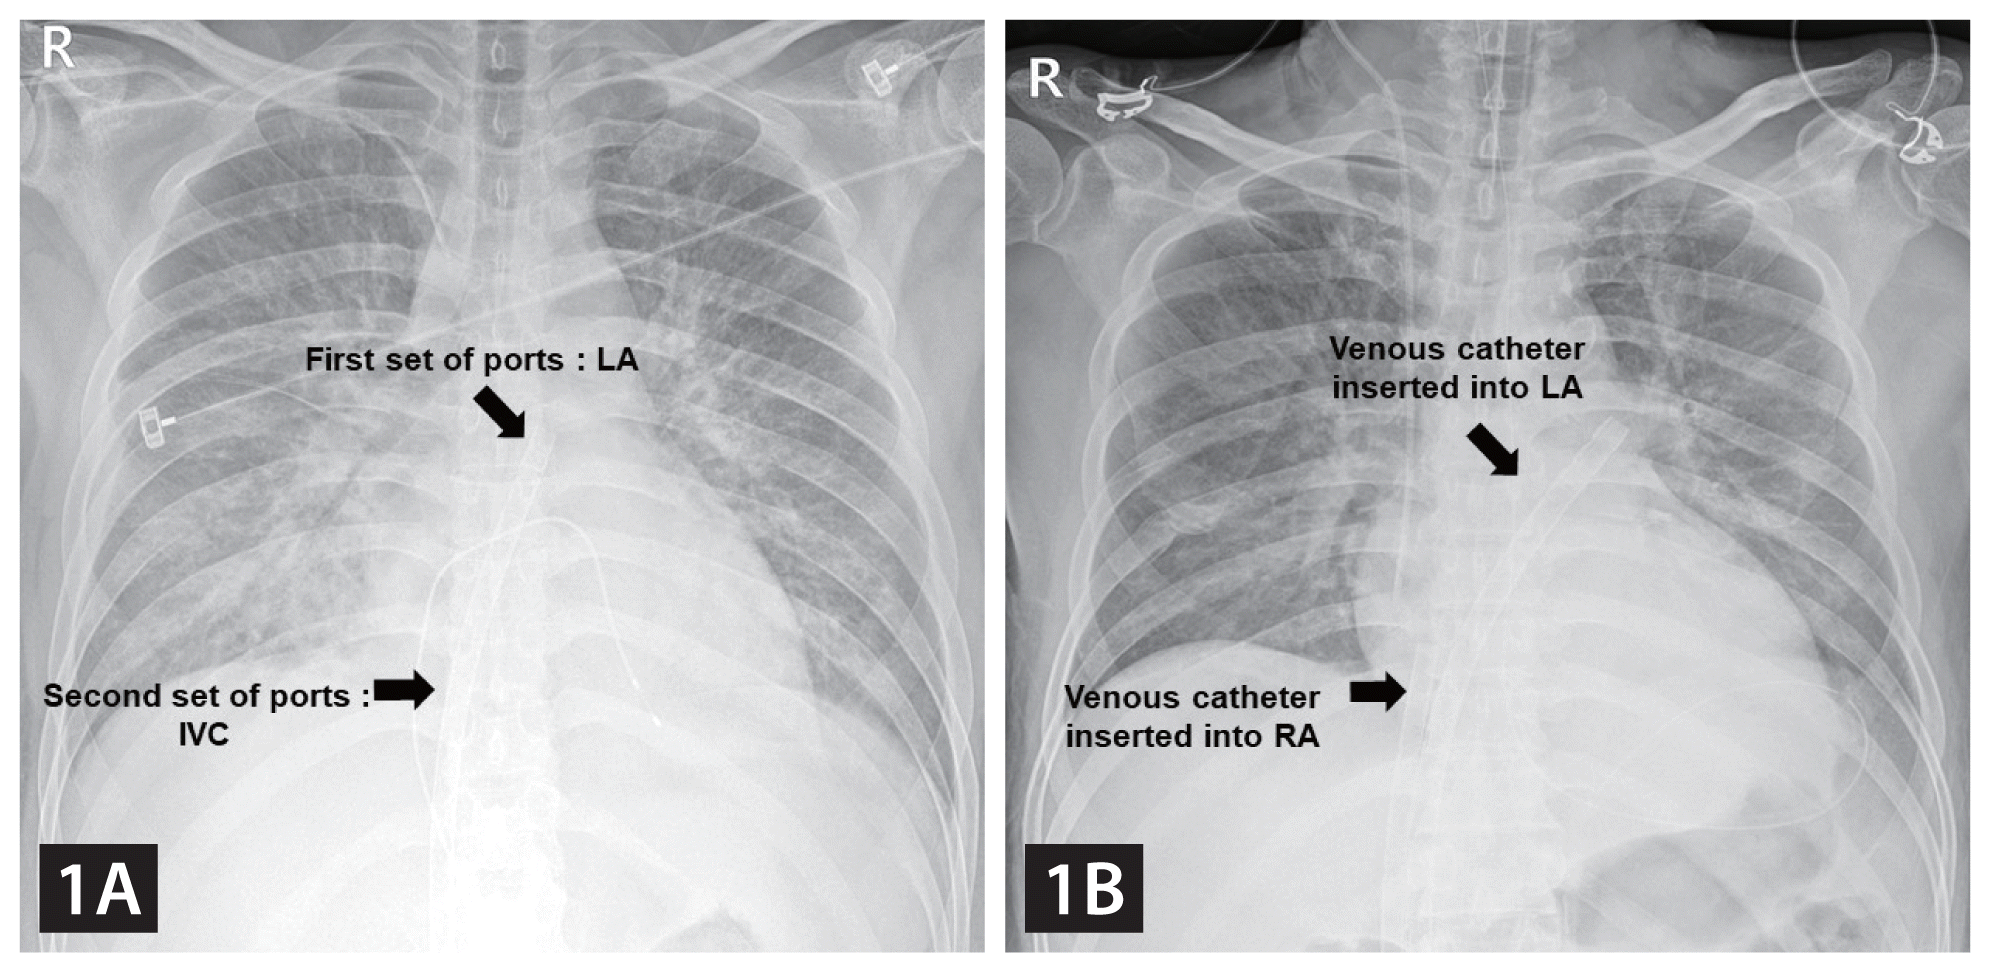

A 42-year-old man, without any previous underlying disease, was transferred to our hospital due to acute myocarditis caused by Coxsackie virus infection. Despite 2 days of supportive care and intravenous inotropic administration, his left ventricular ejection fraction (LVEF; 57%→30%%→10%) and hemodynamic status worsened progressively. Cardiac arrest occurred while preparing for extracorporeal membrane oxygenation (ECMO). Left atrial veno-arterial (VA) ECMO (LA-VA-ECMO) was performed via the right femoral artery and vein for LV unloading. After trans-septal puncturing, a 23-Fr Bio-Medicus NextGen multistage cannula (Medtronic, Minneapolis, MN, USA) was inserted with its tip placed in the left atrium (LA); one set of ports was placed inside the LA for LV venting and the other in the inferior vena cava (IVC) for simultaneous left-sided venting and venous drainage (Fig. 1A). After ECMO insertion, the electrocardiogram showed asystole. However, the patient was alert, and awake ECMO was maintained. Intensive conservative management was conducted, including continuous renal replacement therapy. On the third day, his conduction system recovered. Six days after cannulation, the hemodynamic status improved, and ECMO support was discontinued. Thereafter, LVEF recovered to normal, and he was discharged with outpatient follow-up.

LV unloading is achieved by connecting the left atrial cannula to the inflow limb of a VA-ECMO circuit through a Y connector for biatrial drainage (Fig. 1B, 2B) [1]. The Bio-Medicus NextGen cannula was designed for minimally invasive cardiac surgery, utilizing an advanced multistage design to optimize drainage via the IVC, atrium, and superior vena cava. However, we have effectively used it for LA-VA-ECMO. One set of ports is placed in the LA through a trans-septal puncture and the other in the IVC, allowing effective venous drainage and simultaneous unloading of the LV venting using only one cannula. Moreover, it reduces the risk of vascular complications by eliminating additional vascular access (Fig. 2).

Comparing the use of a multistage cannula with conventional LA-VA-ECMO observed in chest X-ray. (A) Insertion of the Bio-Medicus NextGen multistage venous cannula across the atrial septum. One set of ports is placed in the LA through a trans-septal puncture and the other set in the IVC. (B) Conventional LA-VA-ECMO system. One venous cannula is located in the LA and another in the RA. LA, left atrium; VA, veno-arterial; ECMO, extracorporeal membrane oxygenation; IVC, inferior vena cava; RA, right atrium.